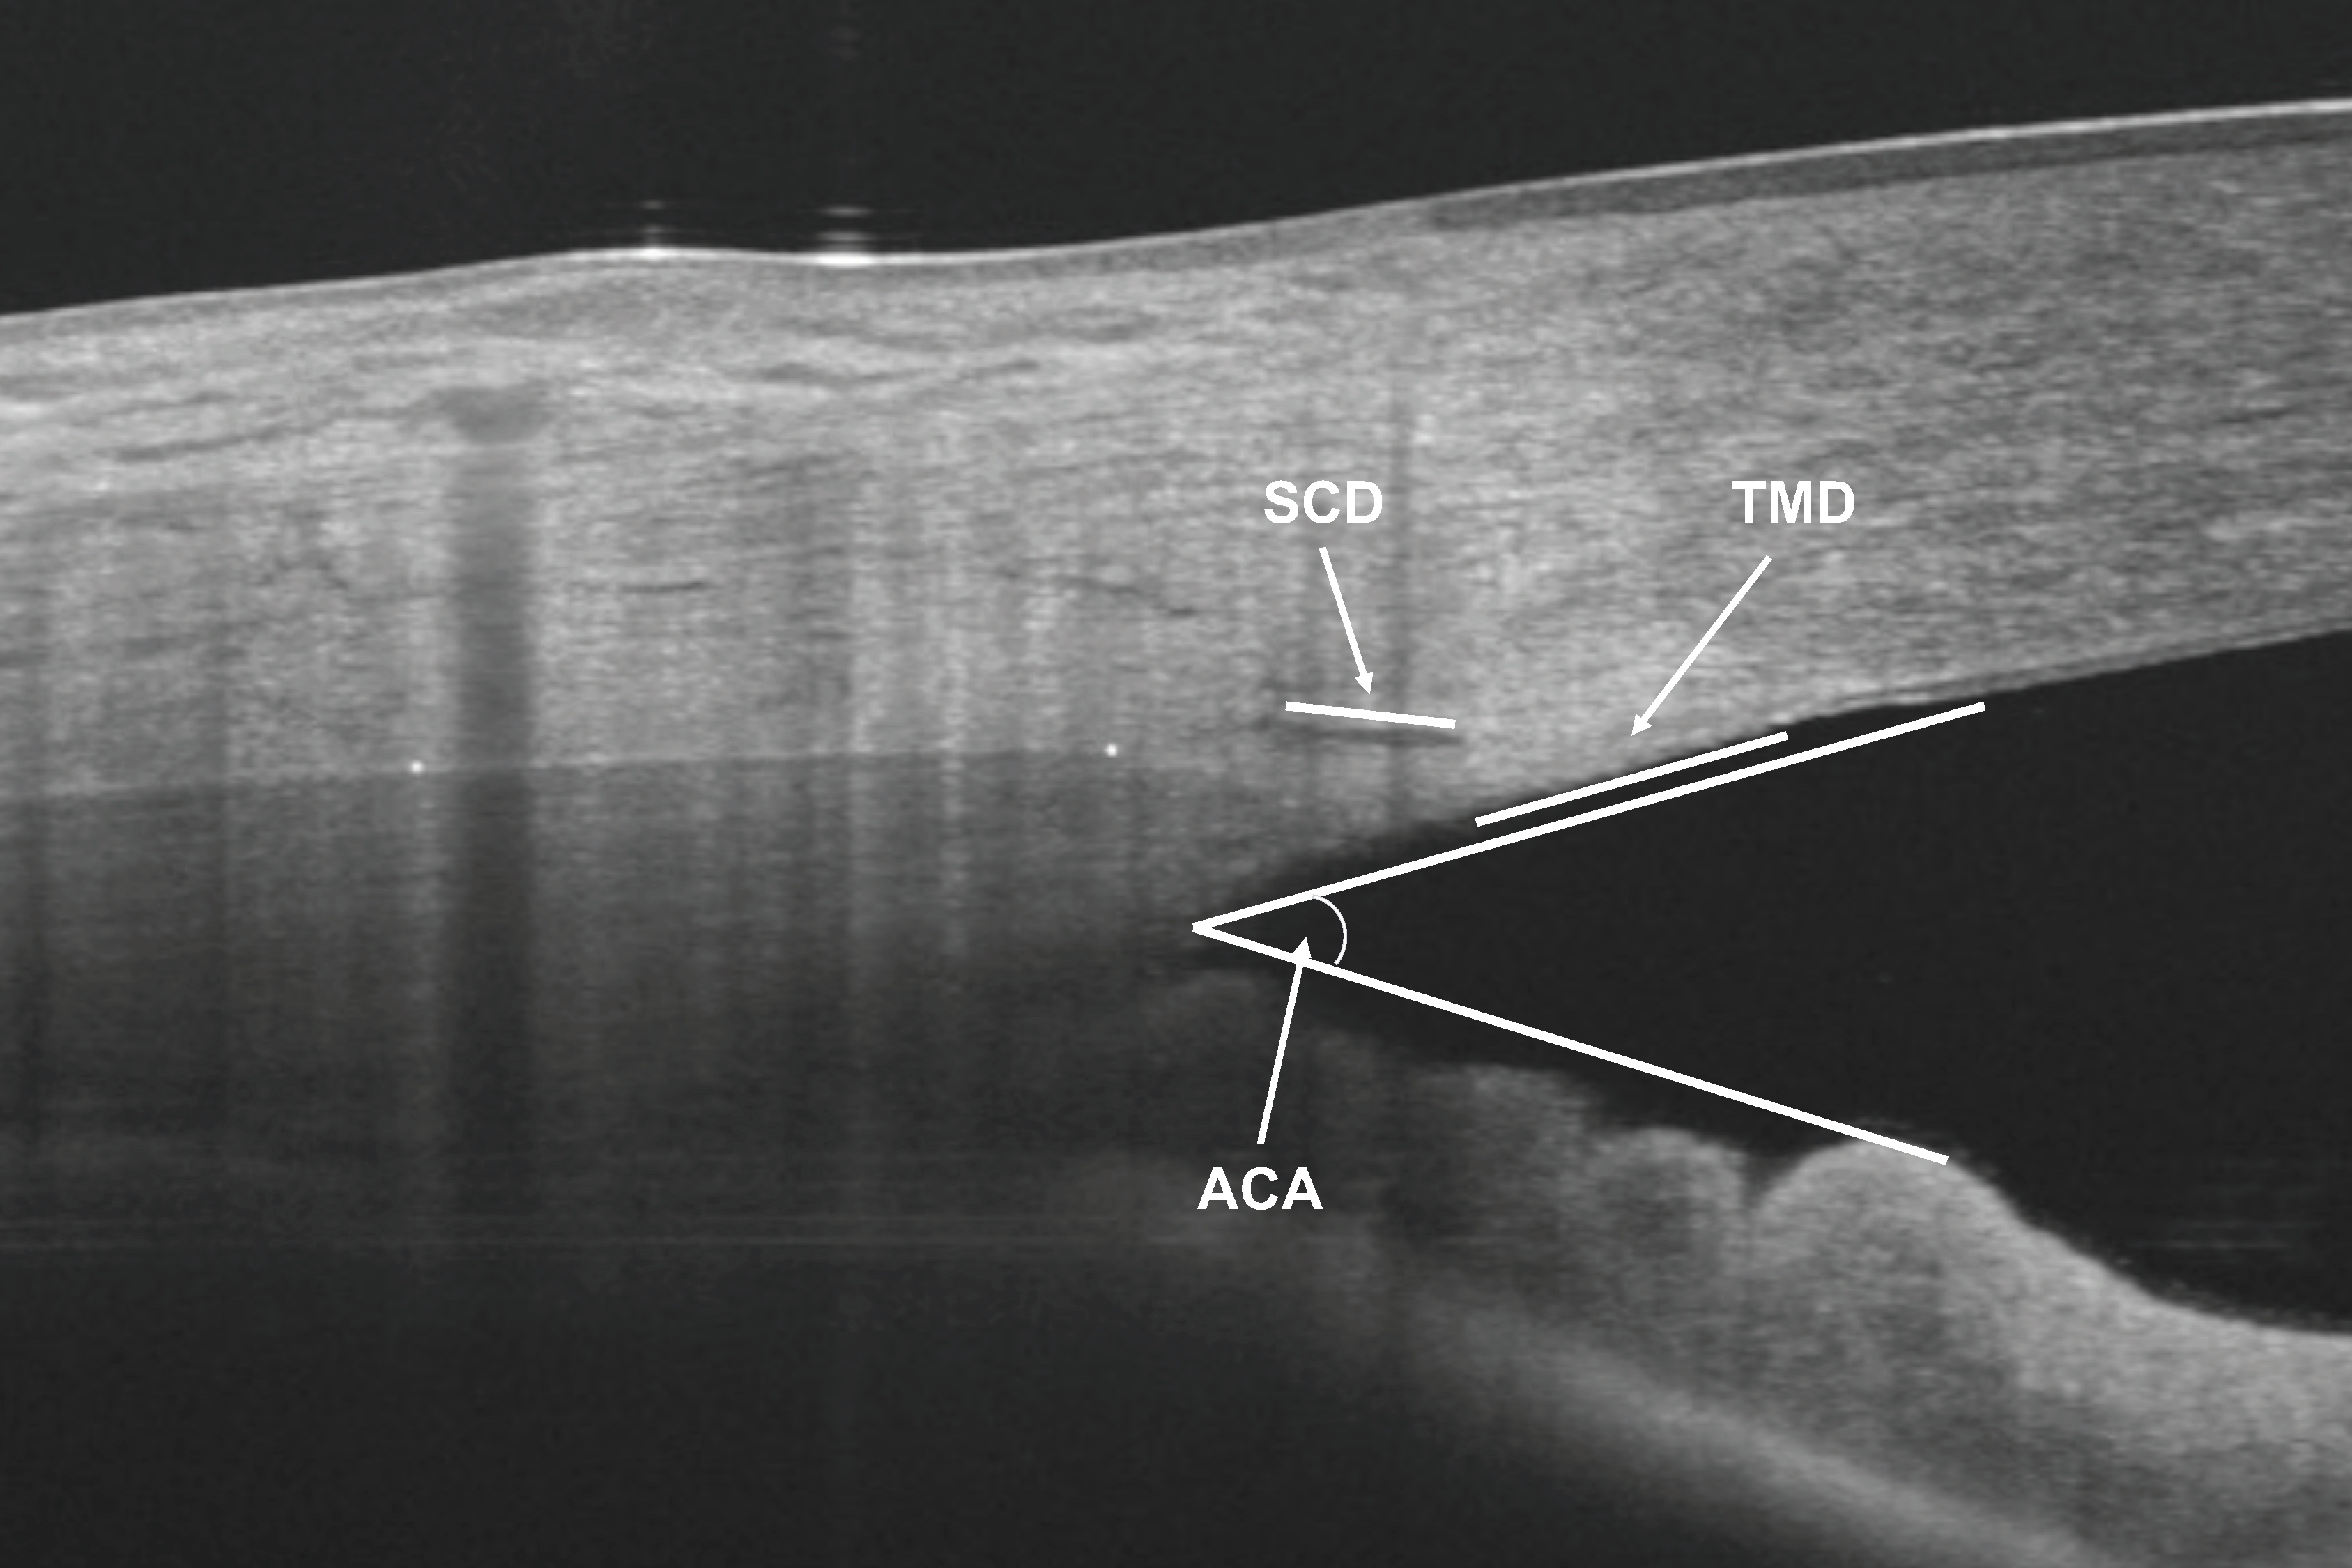

2.3. OCT Measurements